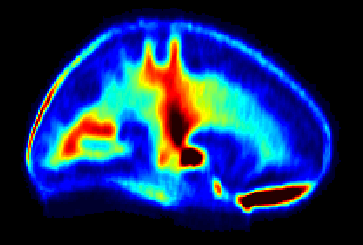

Normative myelin water atlas was created by co-registering and averaging myelin images in MNI space from 50 healthy brains to depict the population mean and variability of the myelin content in the brain. The myelin images of individual subjects were acquired using myelin water imaging. Details about myelin water imaging technique and its analysis can be found here: https://mriresearch.med.ubc.ca/news-projects/myelin-water-fraction/. The created myelin water atlas with its standard deviation can be used as a reference for your own studies related to myelin. A full description of this work can be found in this paper: https://www.ncbi.nlm.nih.gov/pubmed/31347238.

• Myelin water imaging

• Atlas for normal myelin content